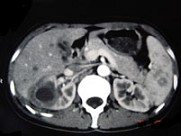

- 多项选择题女,33岁, 右胁腹痛7天,尿检可见大量的脓细胞, CT平扫+增强如图所示,下列说法正确的是 ( )

A、右肾体积增大,其内可见类圆形低密度病灶

B、增强扫描可见该病灶不均匀强化,其内有无强化的坏死灶

C、右肾病灶边界模糊不清

D、考虑为右肾囊肿合并感染

E、考虑为右肾脓肿